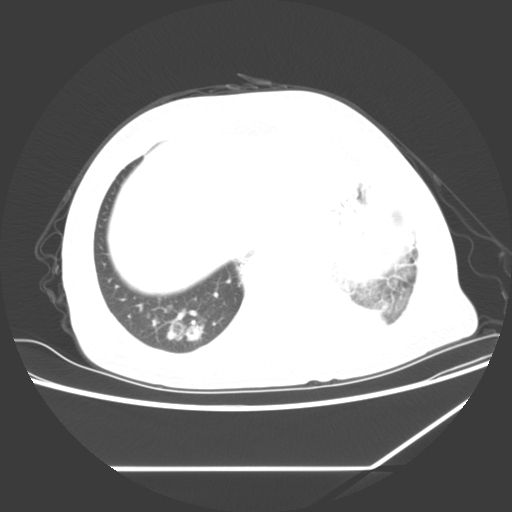

标题: CT25393:病人45岁,咳嗽,吐黄痰带血丝,发热,胸闷月余 [打印本页]

标题: CT25393:病人45岁,咳嗽,吐黄痰带血丝,发热,胸闷月余

1、左肺中央型肺癌并双肺弥漫性转移   2、双肺部感染    3、肺大泡     4、左侧胸腔积液

双侧肺弥漫性病变,可见“空泡征”及“蜂窝征”,考虑肺泡癌可能性大,左侧胸腔积液,考虑胸膜受累可能!

考虑肺泡癌,建议排除感染。

考虑肺泡癌

1)不排除肺泡癌可能。2)左侧胸腔积液。